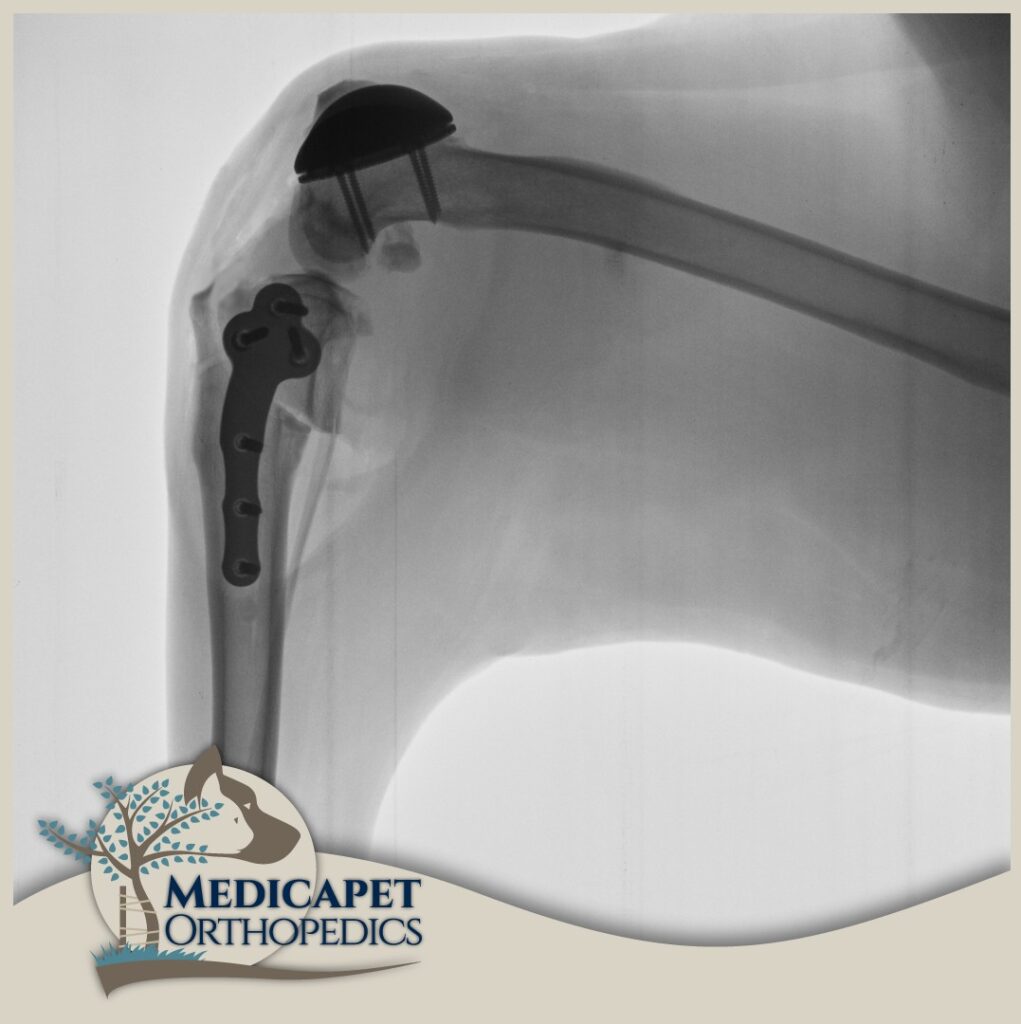

Kaval ve uyluk kemiklerinde ileri derecede eğrilik olan köpeklerin bu kemiklerinin aynı doğrultuya getirilmesini amaçlayan ve düzeltme osteotomileri ile bu kemiklerin doğru pozisyonda yeniden şekillendirildiği işlemlerdir. Daha çok ileri derecede deformasyon olan olgularda uygulanır. Yeniden şekillendirilen uzun kemikler son hallerinde iyileşebilmeleri için plak ve vidalarla sabitlenirler.

PGR (Patellar Groove Replacement)

Aşırı derecede hasar almış Patellar Oluk durumlarında bu oluğun bir protezle değiştirilmesi gerekir. Bu amaçla yüksek teknoloji ile üretilmiş doku uyumlu protezler kullanılır. Türkiye’nin ilk PGR operasyonu merkezimizde yapılmıştır. Şu anda da gerekli vakalarda başarı ile uygulanmaya devam edilmektedir.